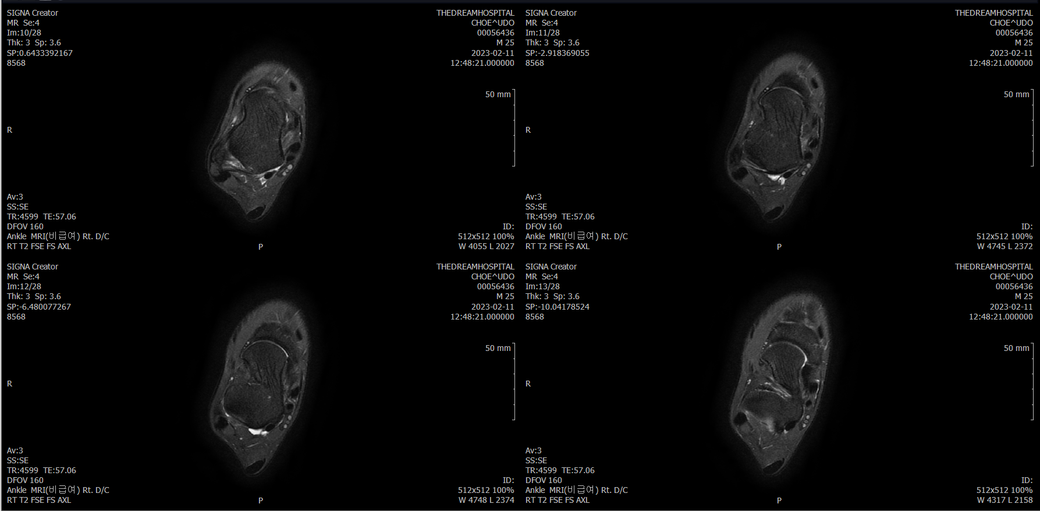

발목 mri 한번 봐주실수 있을까요?

오른발목 mri 전체사진입니다. 제가 병원을 갈수없는상황인지라.... 봐주시면 감사하겠습니다.

엑스레이에서는 문제가 없다고 하여 오른발목 mri촬영했습니다.

우선 전반적으로 봤을 때 큰 이상은 없어보입니다.

전거비인대 등도 저명한 손상은 없는 것 같아 보이지만, 어느 부분의 통증 등으로 인해 촬영을 하셨는지 말씀을 해주신다면 보다 정확한 병변파악이 가능하겠으며, 병원에서 판독이 완료되신다면 전화 등으로 문의를 해보시는 것이 좋겠습니다.